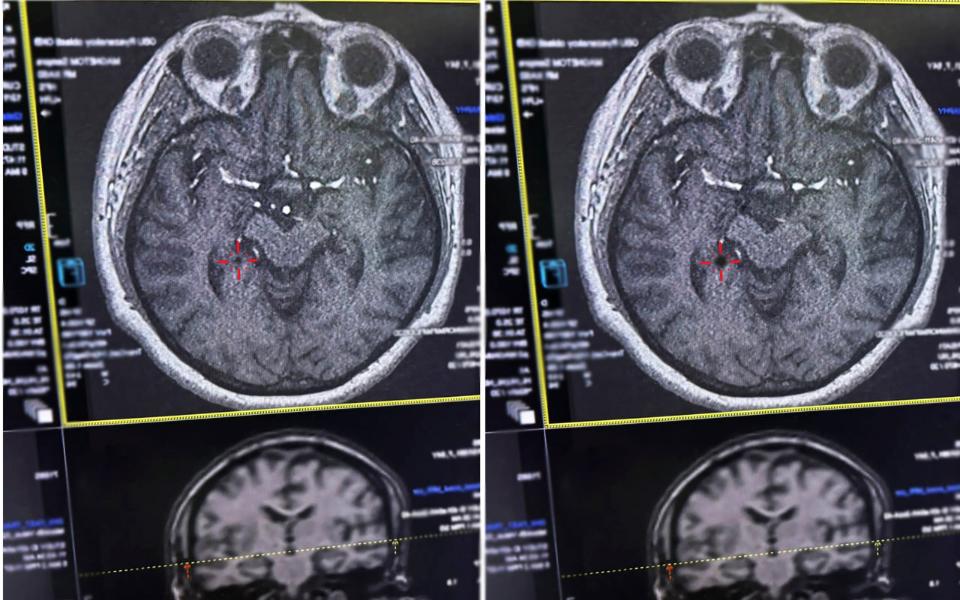

Врачи ОКБ спасли женщину, которая испытала инсульт. Подробности сообщила пресс-служба минздрава Рязанской области.

Женщине стало плохо прямо в магазине. Скорая её госпитализировала. У пациентки перестала двигаться правая стороной тела, она потеряла сознание.

Медики оказали помощь в течение 4,5 часов после начала инсульта. По данным минздрава, врачи сумели попасть в «терапевтическое окно» и сохранить здоровье.